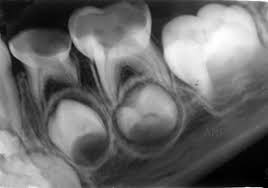

Su frecuencia es de aproximadamente el 12.5%

Factores que

predisponen la reabsorción de los laterales:

· Grado de formación de la raíz del

canino.

· Posición de la cúspide del canino.

· Inclinación vertical del canino.

· Posición del canino en plano sagital.

· Ancho del folículo dentario.

· Grado de reabsorción del canino

temporal.

· Cuando se sitúa por mesial del eje

del lateral el riesgo se triplica.

· Los valores a 25 y 28 grados de ángulos

alfa y beta indican un mayor riesgo.

· En el plano horizontal un ángulo que

supere los 34ª es mayor el riesgo.

Es ideal evaluar radiografías e idealmente tomografía.